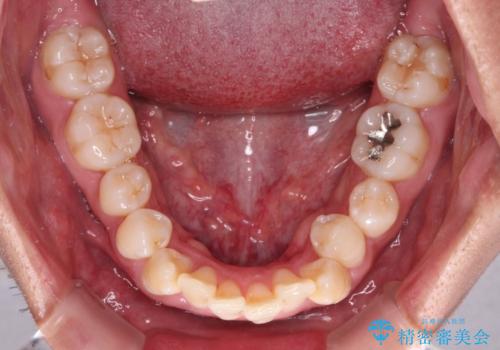

- 八重歯と飛び出している前歯を気にして来院された患者様です。

歯列としてはインビザラインでもワイヤー矯正でも対応できるものでしたが、上顎の八重歯や下顎小臼歯の捻転といったインビザラインでは時間のかかってしまう歯列不正が認められたため、補助装置やワイヤー矯正を治療当初に使用することで、インビザラインによる治療をスムーズに行えるように計画しました。